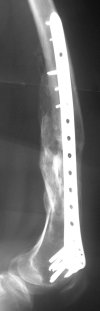

Attached are few examples from our Hospital:

B. Fixation loosening: distal cutting of the nail, non-unions do happen (cases attached).

Locking Plating has more distal screws than any nail, fixed angles and provides much better fixation, especially in osteoporotic bone.

Again, Locking Plating is minimally invasive, SUBCUTANEOUS INTERNAL FIXATION and I believe for the most surgeons preferred method of treatment for distal femur fractures (I do not have any financial interest with any of the manufacturers, parties).

A new toy is more interesting and fashionable. And anyway it is not panacea, i have already seen presentations with LISS failures like the attached one presented by D.Seligson. And people also demonstrated incisions say that the method is not so LESS invasive as it supposed to be.